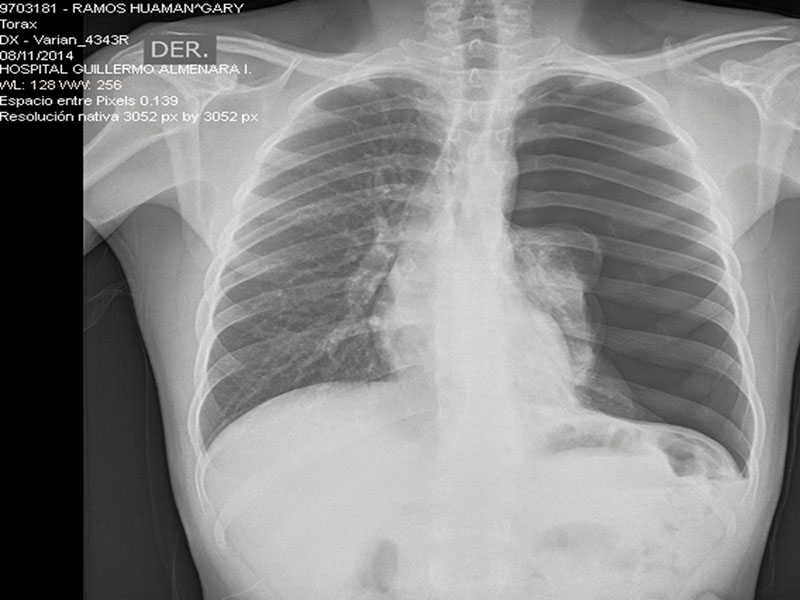

Luego de una historia clínica y examen clínico minucioso y apoyado en una radiografía de tórax se llega al diagnóstico.